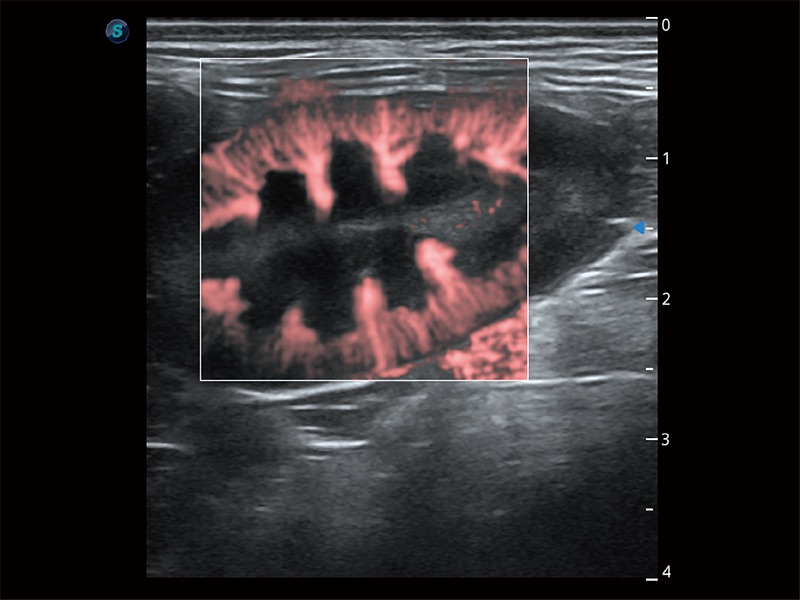

极大提升超低速微细血流的检出能力,同时更精准地滤除软组织和超声信号,为兽用医生提供以往无法通过常规血流获得的疾病诊断信息。

在传统二维血流成像的基础上,呈现血流的立体感,具有动感的生命力之美。即便是微小的血管也能轻松应对,提高了血流的视觉敏感性。